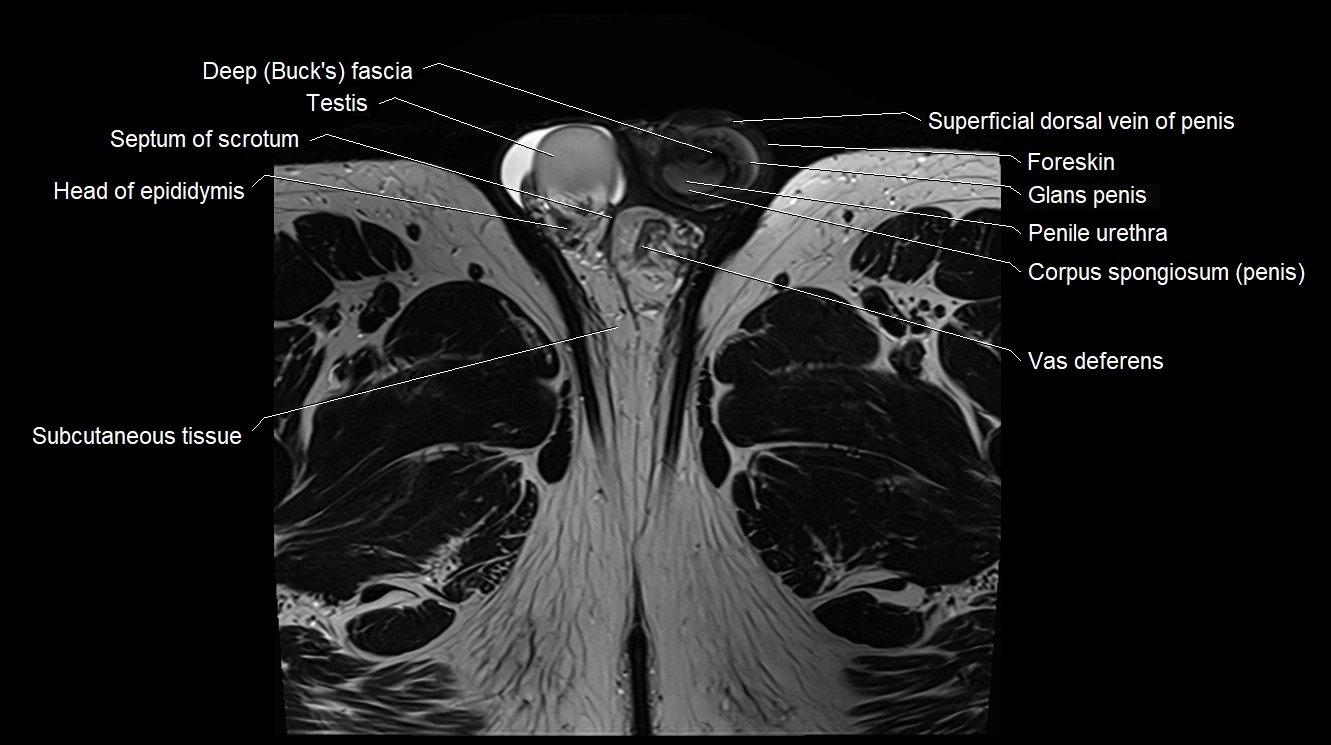

- Buck's fascia (Deep fascia of penis)

- Foreskin

- Glans penis

- Head of epididymis

- Penile urethra

- Septum of scrotum

- Subcutaneous tissue (scrotum)

- Superficial dorsal vein of penis

- Testis

- Vas deferens